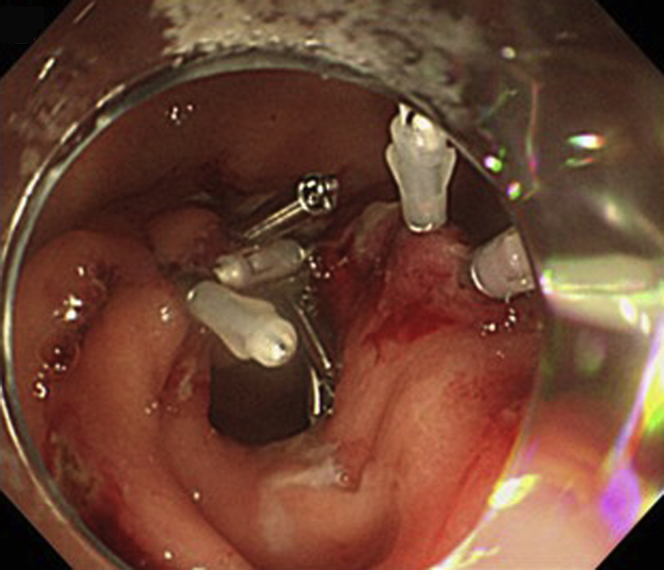

Figure 7.

Transverse closure of the longitudinal incision with hemoclips.